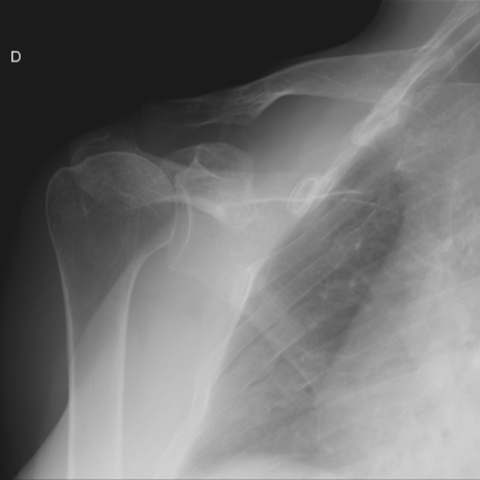

一年前肩关节平片未见确切骨质异常。

1623864b0e61ea9de14ecb324ed06575.png